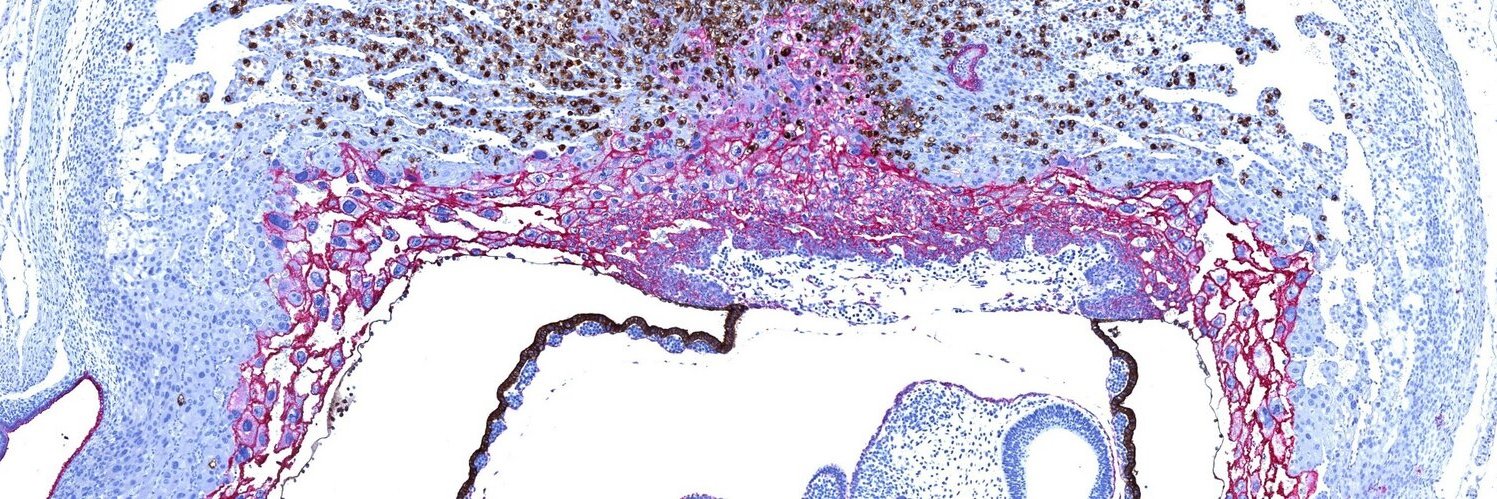

Delighted to contribute to this epic review with colleagues @ObsGynaeCam and @ProfStephenTong. @Loke_CTR The human placenta and its role in reproductive outcomes revisited | Physiological Reviews | American Physiological Society journals.physiology.org/doi/abs/10.115…